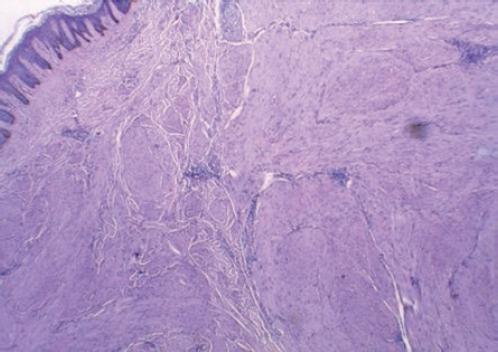

Varón de 32 años, con obesidad de grado II, antecedente de piloleiomiomatosis y de hipertensión arterial sistémica, tabaquismo positivo. Presentó hematuria total no formadora de coágulos sin condicionar retención aguda de orina, con remisión espontánea. La tomografía computarizada contrastada reveló un tumor dependiente del riñón derecho, heterogéneo, lobulado, irregular, de 179 × 147 × 165 mm, con realce hasta 120 UH; glándula suprarrenal izquierda de 57 × 43 × 20 mm, con realce hasta 80 UH (Fig. 1); tórax sin lesiones. Se realizaron nefrectomía radical derecha y adrenalectomía izquierda, con reporte histopatológico en el producto de la nefrectomía de carcinoma renal papilar de tipo II (Fig. 1), y en el producto de la adrenalectomía de adenoma suprarrenal. La tomografía computarizada de control posquirúrgico a los 2 meses no mostró datos de actividad tumoral. Al sexto mes de seguimiento se realizó una tomografía por emisión de positrones (PET) (Fig. 2) que evidenció una lesión en el segmento hepático VI con SUV (standardized uptake value) máximo de 7.8, con dimensiones de 18 × 13 mm, adenomegalias retrocavas, paracavas e interaortocavas, lobuladas, con SUV máximo de 14, de hasta 9 mm. Testículos con lesiones con incremento de metabolismo, predominio izquierdo con lesión de 15 × 13 mm, con SUV máximo de 8.6. El ultrasonido testicular (Fig. 3) evidenció lesiones hipoecoicas bilaterales, la mayor en el lado izquierdo, con ligero aumento del flujo a la aplicación de Doppler. Los marcadores tumorales fueron: alfa-fetoproteína 7.84, gonadotropina coriónica humana fracción beta < 1.20, lactato deshidrogenasa 155. Se realizó orquiectomía radical izquierda con reporte histopatológico de tumor de células de Leydig (Fig. 4) de 2 cm, con inhibina (+), calretinina (+), vimentina (+) y sinaptofisina (−), sin invasión linfovascular, y biopsia de lesión en muslo izquierdo con reporte de leiomioma (Fig. 5). La tomografía computarizada de tórax mostró múltiples lesiones de 2-5 mm de diámetro con realce al medio de contraste. En el abdomen se observan dos imágenes sólidas que presentan realce anular y necrosis central, de 60 × 50 mm, en segmento VII hepático, y de 45 × 30 mm en el segmento VI. El lecho quirúrgico derecho muestra imágenes hipodensas, redondeadas, de aspecto nodular, de 15 mm. La biopsia de la lesión hepática reporta necrosis, y la biopsia retroperitoneal presencia de células neoplásicas, sin poder establecer el tipo histológico. Se realizó tumorectomía y metastasectomía hepática, con reporte histopatológico de lesión hepática y retroperitoneal con metástasis por carcinoma papilar de tipo 2. Inmunohistoquímica con CD 10 positivo y CK 7 negativo (Fig. 6). En el último estudio de seguimiento no hay datos de actividad tumoral y actualmente se encuentra en vigilancia oncológica y manejo con sunitinib.

Figura 5 Producto de biopsia de lesión en el muslo, corte con tinción de hematoxilina-eosina que muestra células fusiformes, alargadas, de músculo liso, profundas.